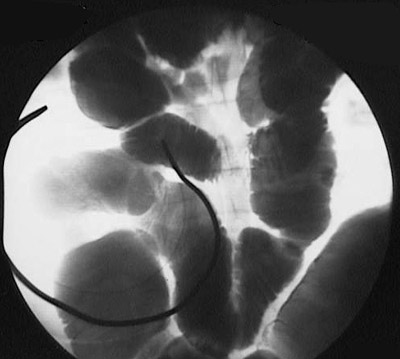

The upper GI series radiograph above reveals a focal area of narrowing from thickening with inflammation of the terminal ileum, consistent with Crohn's disease.